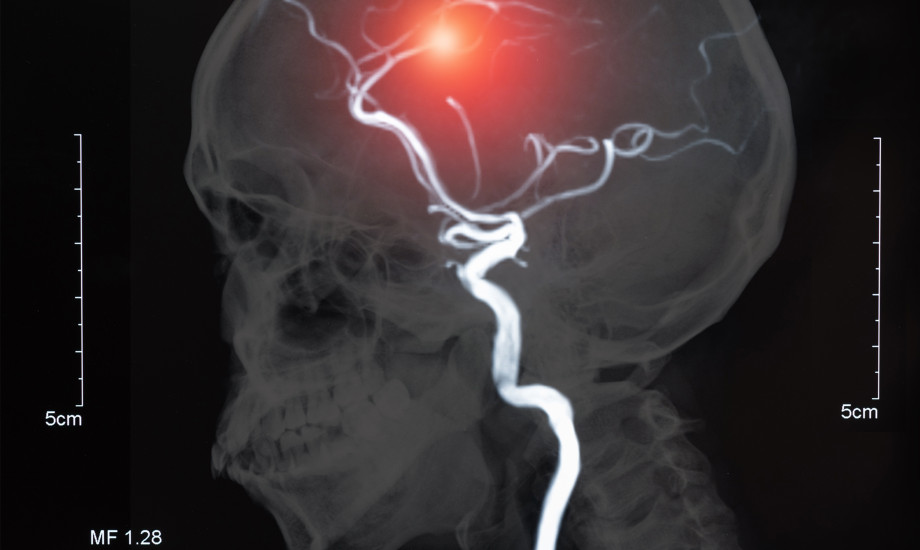

Troponin auch bei Schlaganfall-Patienten nützlich

Der Blutmarker Troponin eignet sich auch bei Patienten mit einem Schlaganfall, um einen Herzinfarkt besser zu erkennen. Das zeigt nun das Ergebnis der PRAISE-Studie.